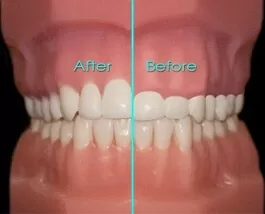

Khi nào cần phẫu thuật làm dài thân răng? Răng của bạn có thể không ngắn nhưng bị che phủ bởi quá nhiều mô nướu. Để cải thiện tình trạng này nha sĩ có thể tiến hành phẫu thuật làm dài thân răng.

Trong quá trình phẫu thuật, mô nướu và xương sẽ được điều chỉnh để bộc lộ nhiều hơn thân răng tự nhiên. Phẫu thuật có thể tiến hành ở 1 răng để tạo vẻ hài hòa của đường viền nướu hoặc nhiều răng để nụ cười của bạn đẹp hơn.